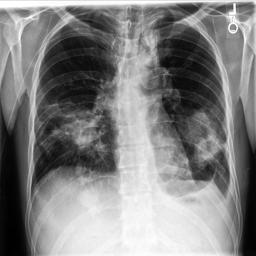

Large numbers of labeled medical images are essential for the accurate detection of anomalies, but manual annotation is labor-intensive and time-consuming. Self-supervised learning (SSL) is a training method to learn data-specific features without manual annotation. Several SSL-based models have been employed in medical image anomaly detection. These SSL methods effectively learn representations in several field-specific images, such as natural and industrial product images. However, owing to the requirement of medical expertise, typical SSL-based models are inefficient in medical image anomaly detection. We present an SSL-based model that enables anatomical structure-based unsupervised anomaly detection (UAD). The model employs the anatomy-aware pasting (AnatPaste) augmentation tool. AnatPaste employs a threshold-based lung segmentation pretext task to create anomalies in normal chest radiographs, which are used for model pretraining. These anomalies are similar to real anomalies and help the model recognize them. We evaluate our model on three opensource chest radiograph datasets. Our model exhibit area under curves (AUC) of 92.1%, 78.7%, and 81.9%, which are the highest among existing UAD models. This is the first SSL model to employ anatomical information as a pretext task. AnatPaste can be applied in various deep learning models and downstream tasks. It can be employed for other modalities by fixing appropriate segmentation. Our code is publicly available at: https://github.com/jun-sato/AnatPaste.

翻译:大量贴有标签的医学图像对于准确检测异常现象至关重要,但人工注解是劳动密集型和耗费时间的。自监学习(SSL)是一种培训方法,用于在不人工注解的情况下学习特定数据特征。一些基于SSL的模型被用于医学图像异常现象的检测。这些SSL方法有效地学习了多个特定领域图像的表解,如自然和工业产品图像。然而,由于医学专业知识的要求,基于SSL的典型模型在医学图像异常现象检测方面效率低下。我们展示了一个基于SSL的模型,可以进行基于解剖结构的、不受监督的异常现象检测(UAAD)。该模型使用解剖-觉粘贴(AnatPaste)增强工具。基于SSL的几种模型用于医学图像异常现象。这些异常现象与真正的异常相似,有助于模型识别这些异常现象。我们在三种开源的胸腔辐射数据集中可以使用模型,在基于解剖面结构结构的曲线下(AUSC),在92.1号中使用解析(Anal-SL)粘度图解为最高格式。